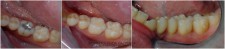

LIJEVO: 1a početno stanje,prednji zubi - DESNO: 1b nakon završetka terapijee LIJEVO: 2a revizija punjenja korijenskih kanala,višekorijenski zubi        <br />

DESNO: 2b nakon završetka terapije LIJEVO: 3a  prije revizije punjenja,jednokorijenski zub<br />

DESNO: 3b  nakon završetka terapije LIJEVO: 4a liječenje granuloma ,početno stanje<br />

SREDINA: 4b stanje nakon 9 mjeseci<br />

DESNO: 4c stanje nakon 3 godine, granuloma više nema !